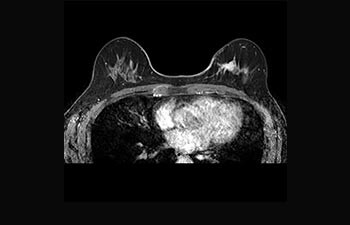

Mayor fiabilidad diagnóstica en neurooncología